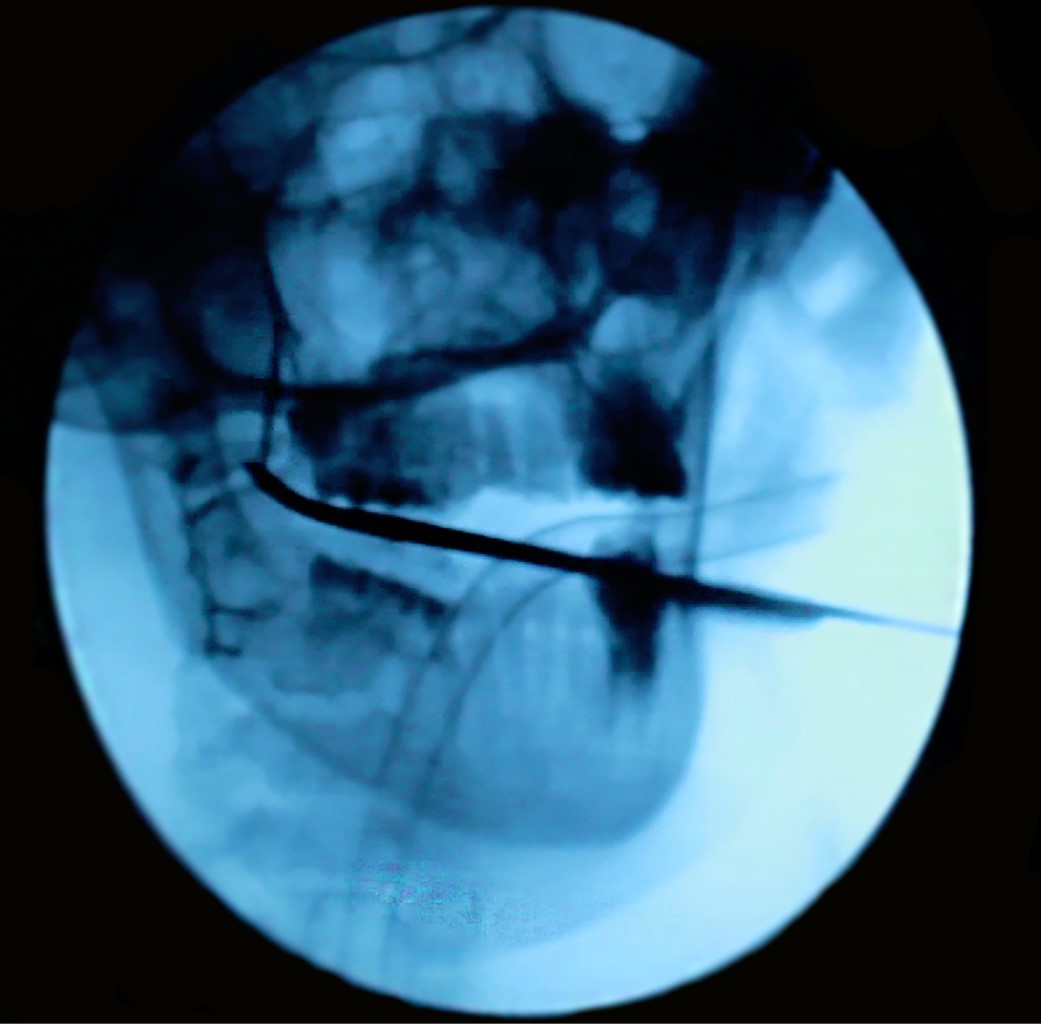

Se realizó el retiro del CE mediante el fluoroscopio en sala de operaciones con un abordaje mínimamente invasivo en fondo de vestíbulo, pudiendo encontrar y remover exitosamente el CE de la FP derecha (Figuras 4 y 5). Posteriormente, se trató a la paciente mediante una férula miorrelajante, acompañada de fisioterapia por un lapso de cuatro meses, logrando así la recuperación de la apertura bucal, 35 milímetros aproximadamente (Figura 6). Es importante mencionar que entre el CE y los tejidos blandos circundantes se formó un área de tejido fibroso, la cual estaba condicionando la limitación de la apertura bucal. Se tomaron radiografías de control, las cuales evidenciaron la correcta consolidación de la fractura de ángulo derecho (Figura 7). Finalmente, la paciente fue transferida a ortodoncia para realizarse el tratamiento ortoquirúrgico de la maloclusión clase III.

La resolución de estos casos atípicos es muy variada y dependerá también de la tecnología que tenga a disposición el cirujano maxilofacial para el retiro del CE.3 En caso de que el cuerpo extraño esté muy próximo a las arterias carótidas, el enfoque idóneo es el empleo de la angiografía con sistema de navegación, para lo cual es importante previamente calibrar los instrumentales a ser empleados con la TEM.10 En este caso, el uso del fluoroscopio permitió conocer la información en tiempo real sobre el posicionamiento del material de osteosíntesis de manera segura, por lo que esta técnica se mantiene vigente; además, cabe mencionar que éste es empleado a manera de rutina en traumatología.4